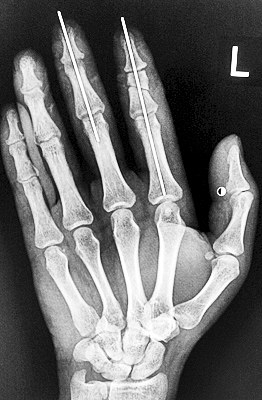

術(shù)后X光顯示,骨骼對(duì)位良好。

最終,盧微波和團(tuán)隊(duì)找好了需要的血管和神經(jīng),做好標(biāo)記后,開始固定食指骨骼、吻合肌腱,最后在顯微鏡下用直徑20微米的無(wú)創(chuàng)顯微縫合線開始吻合血管和神經(jīng)。

在經(jīng)過兩個(gè)多小時(shí)手術(shù)后,早上8時(shí)許,盧微波下令松止血帶,數(shù)十秒后男子蒼白的食指逐漸紅潤(rùn)起來(lái),食指在離體10個(gè)小時(shí)后恢復(fù)血運(yùn)。

緊接著,盧微波又開始中指再植手術(shù)。上午10時(shí)許,中指在離體12小時(shí)后也成功恢復(fù)血運(yùn)。